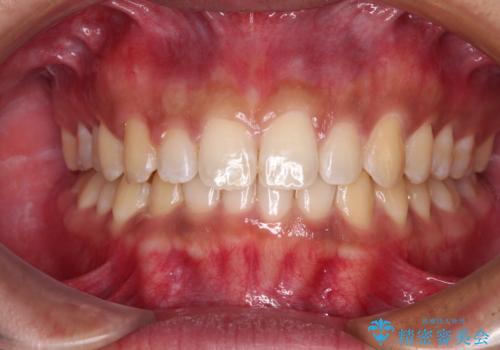

- 前歯のデコボコや隙間と深い咬み合わせ(ディープバイト)を気にして来院された患者様です。

インビザラインによる上下歯列の側方拡大と後方移動、IPR(歯と歯の間を削る)にるスペースの獲得により、デコボコとディープバイトを改善することとしました。

気になっていたデコボコや隙間は改善し、きれいな歯列に整えることができました。

咬合力が非常に強い方であったため、これ以上のディープバイトの改善は困難となりました。